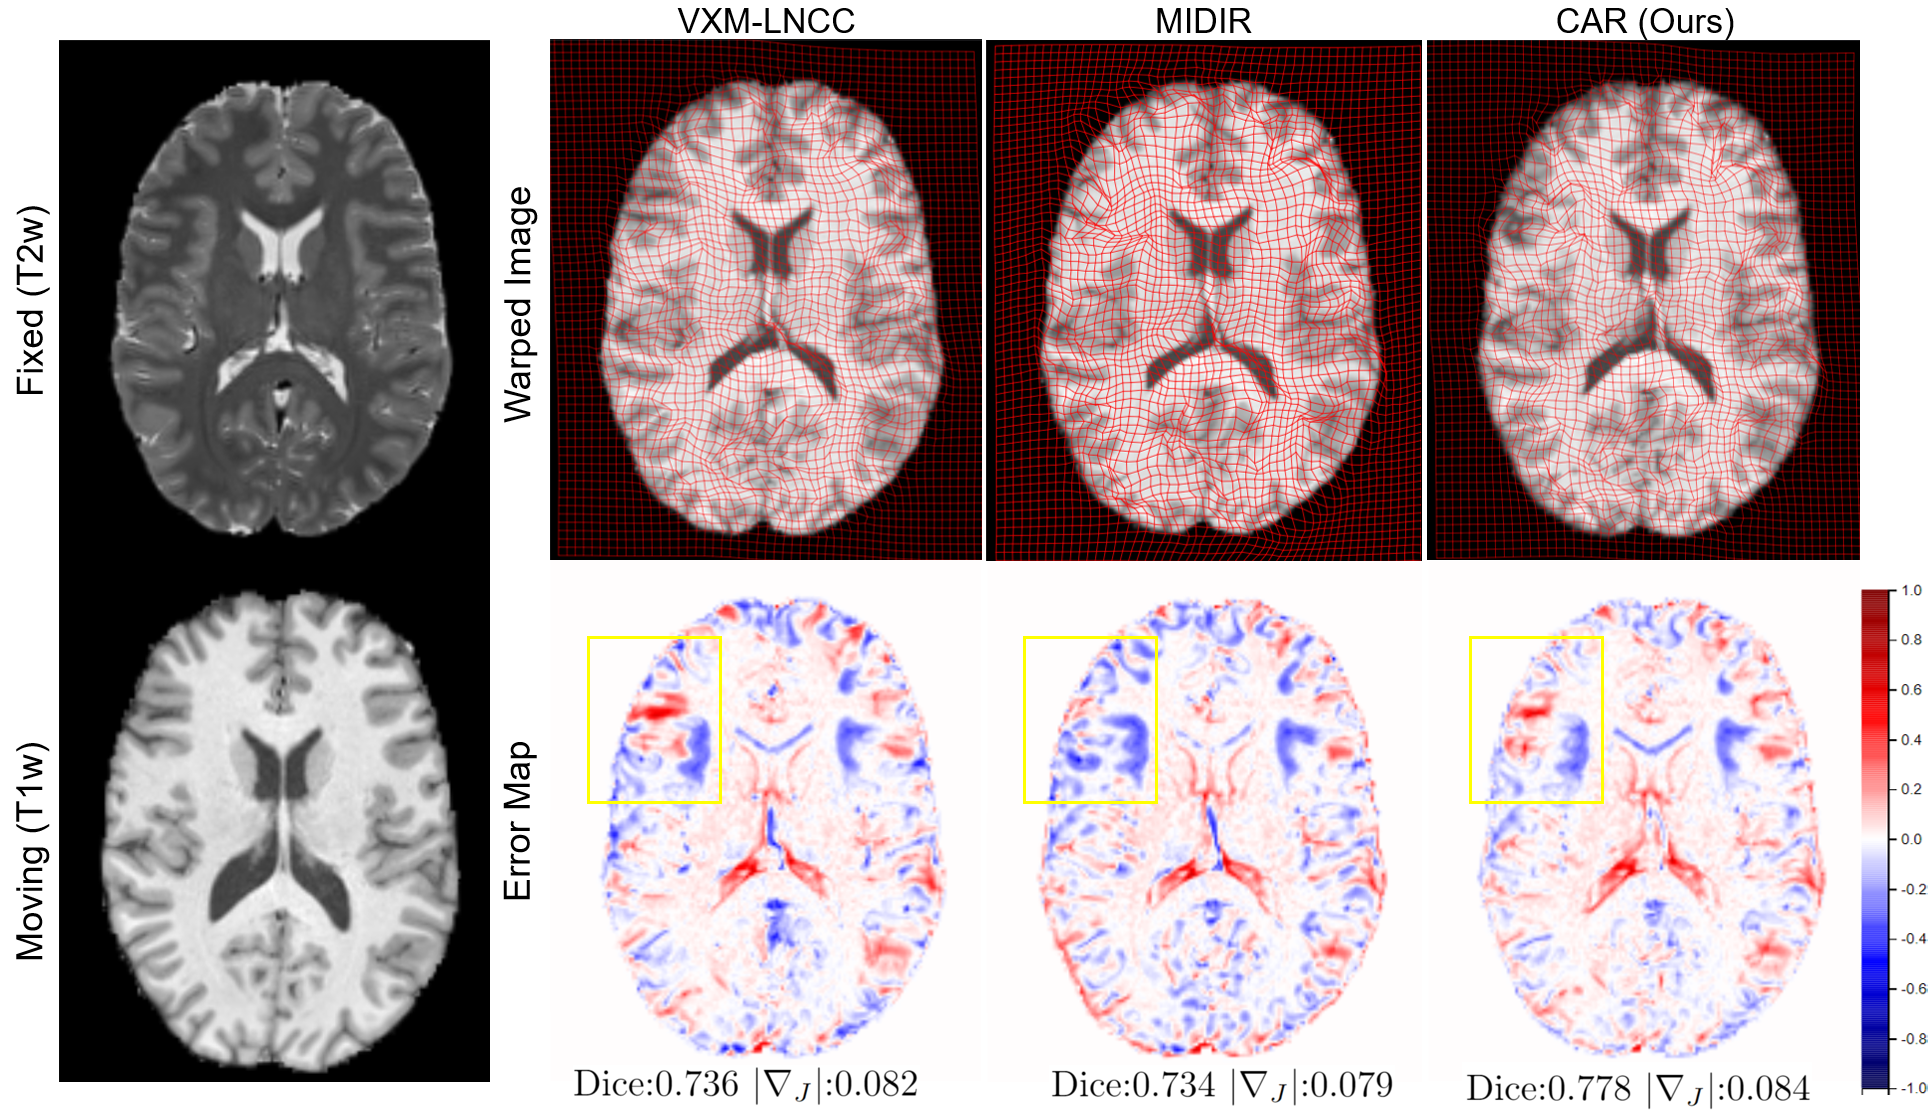

Figure 2: Qualitative results on CamCAN dataset.

A quantitative comparison result on both brain MRI and cardiac MRI is summarized in Table 1. For the cardiac registration task, the result is reported for registering misaligned images of TIi=2:9subscriptTI:i29\mathrm{TI_{i=2:9}} to TI1subscriptTI1\mathrm{TI_{1}}. It can be observed that CAR achieves the best registration accuracy while possessing good deformation regularity for both tasks. For the brain MRI registration task, CAR demonstrates superior generalization ability as CAR only used T1w images for training but performed the best on the T1w-T2w registration task for all learning-based approaches in terms of registration accuracy and deformation regularity. This is similar to the cardiac registration task when our model was trained using only TI1subscriptTI1\mathrm{TI_{1}} image but can be generalized to all other contrasts of images in T1 Mapping data. It can be noted that CAR has the lowest folding ratio. This is because we are dealing with nine different weightings of T1 images and the learned contrast-invariant representations may help the network get a more stable solution from images with different contrasts. Fig 2 and Fig 3 also show the qualitative comparison results of brain and cardiac registration tasks respectively, demonstrating that CAR can achieve low registration error and smooth deformation field. Both figures also show that CAR can register more fine-grained details than baseline approaches, which are shown in the highlighted regions.